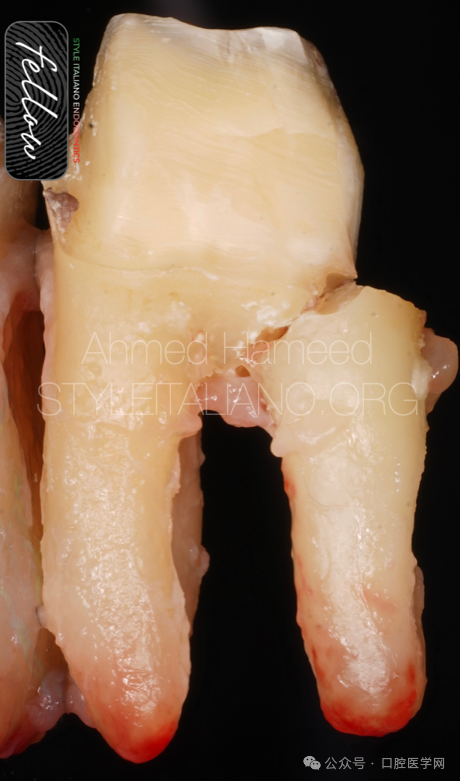

图11

这张照片显示了裂纹如何向下延伸到骨头,这意味着这可能是一个垂直的裂,它需要被拔除。

我们可以清楚地看到牙齿完全劈裂,这意味着除了拔除,没有什么好做的了。

图12 拔除是这里唯一的治疗方式。